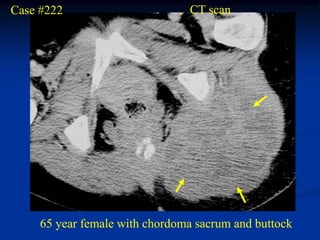

Case #222                       CT scan

65 year female with chordoma sacrum and buttock

tumor

Axial T-2 MRI

Axial T-2 MRI at higher level

femur

Sagittal T-2 MRI